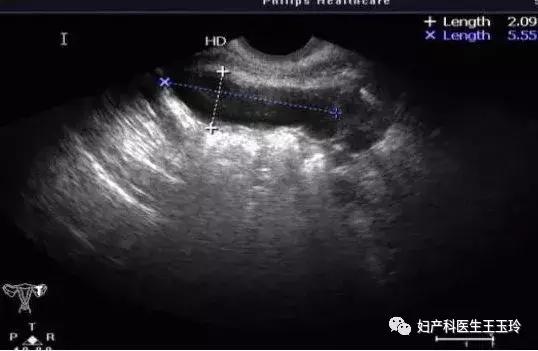

输卵管积液的超声表现

输卵管在没有积液的情况下,超声难以观察,所以超声报告从不会描述输卵管。一旦输卵管有积液,超声下就可以看到输卵管。可见,能被看到并非好事。

输卵管积液,在超声下常常描述为:卵巢旁长条状的、腊肠状的无回声。

从超声上可以看到输卵管结业和卵巢囊肿区别:

卵巢囊肿在卵巢内,输卵管积液在卵巢旁;长条状正好和输卵管的性状吻合。腊肠状说明输卵管外常常也有粘连,所以导致输卵管的积液不规则;无回声,说明输卵管内部是水样的液体,而卵巢肿瘤也可以弱回声、混合回声。